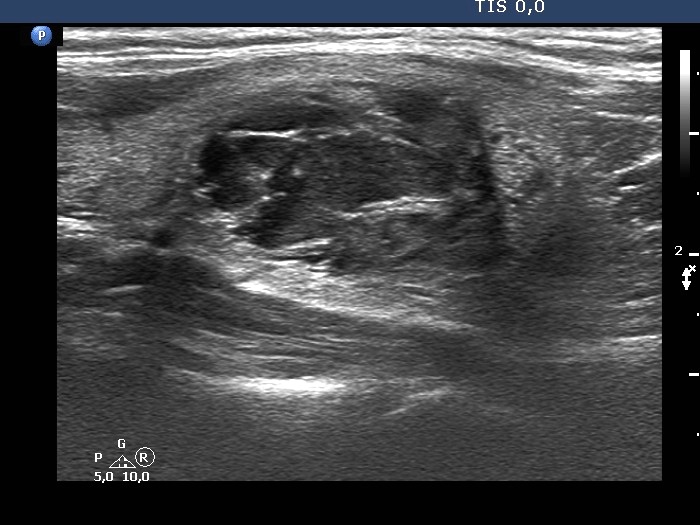

The composition of the nodule - case 142 |

Ultrasonography. The thyroid was echonormal. There were multiple cystic areas and nodules in both lobes. The smaller cystic lesions in the right lobe were cystic areas, i.e. dilated macrofollicles. The largest lesion was a peripheral-type cystic nodule. The nodule in the upper part of the left lobe was a peripheral-type cyst, while the lower lesion had around 50% cystic and 50% solid areas.We aspirated 2.8 mL brown fluid from the peripheral type cyst, thereafter an US-guided aspiration was performed from the solid part. Aspiration cytology resulted in benign cystic lesion.

Ultrasonography. The presentation remained unchanged except for two conditions. Firstly, the cystic nodule in the right lobe has slightly increased while the cystic nodule in the upper part of the left lobe has significantly decreased, i.e. it has not refilled.Suggestion: ultrasound in three years.

Comment. This case illustrates the difference between cystic areas and cystic nodules in pathological sense. The former are pure cysts with small size and correspond to dilated macrofollicles. The nodule is the lower part of the left lobe was difficult-to-categorize because it contained in equal proportions cystic and solid areas.